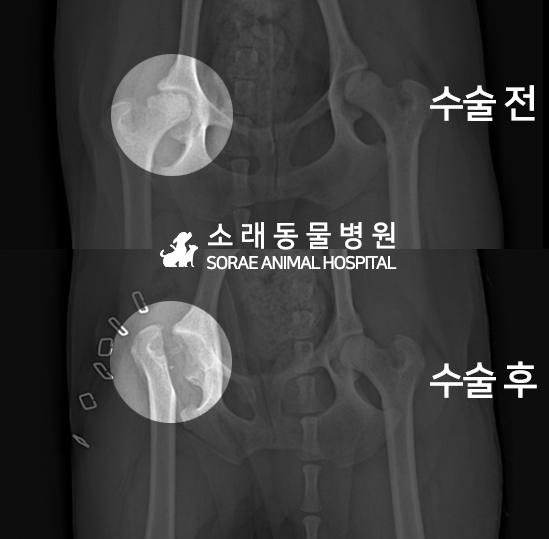

고관절 수술 사례 - #282 쿠키

쿠키는 고관절 수술 상담을 위해 내원하였습니다.

촉진 및 방사선 촬영 결과

대퇴골두 절골술(FHNO)이 필요하다고 판단되었습니다.

문제의 원인이 되는 대퇴골두를 깔끔하게 절단해 주었습니다.

수술 전과 수술 후 촬영한 고관절 방사선 사진입니다.

대퇴골두가 깔끔하게 절단된 것이 확인됩니다.

이제 재활 운동을 통해 체중을 지지할 근육을 키워주게 됩니다.